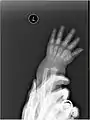

The five metacarpal bones, numbered. Left hand, anterior (palmar) view.

os primum metacarpale / os metacarpale I

os secundum metacarpale / os metacarpale II

os tertium metacarpale / os metacarpale III

os quartum metacarpale / os metacarpale IV

os quintum metacarpale / os metacarpale V